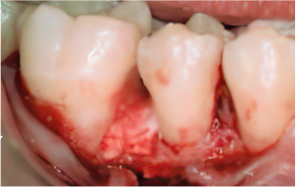

-

STEP 06

Flap closure and suturing

Before & After